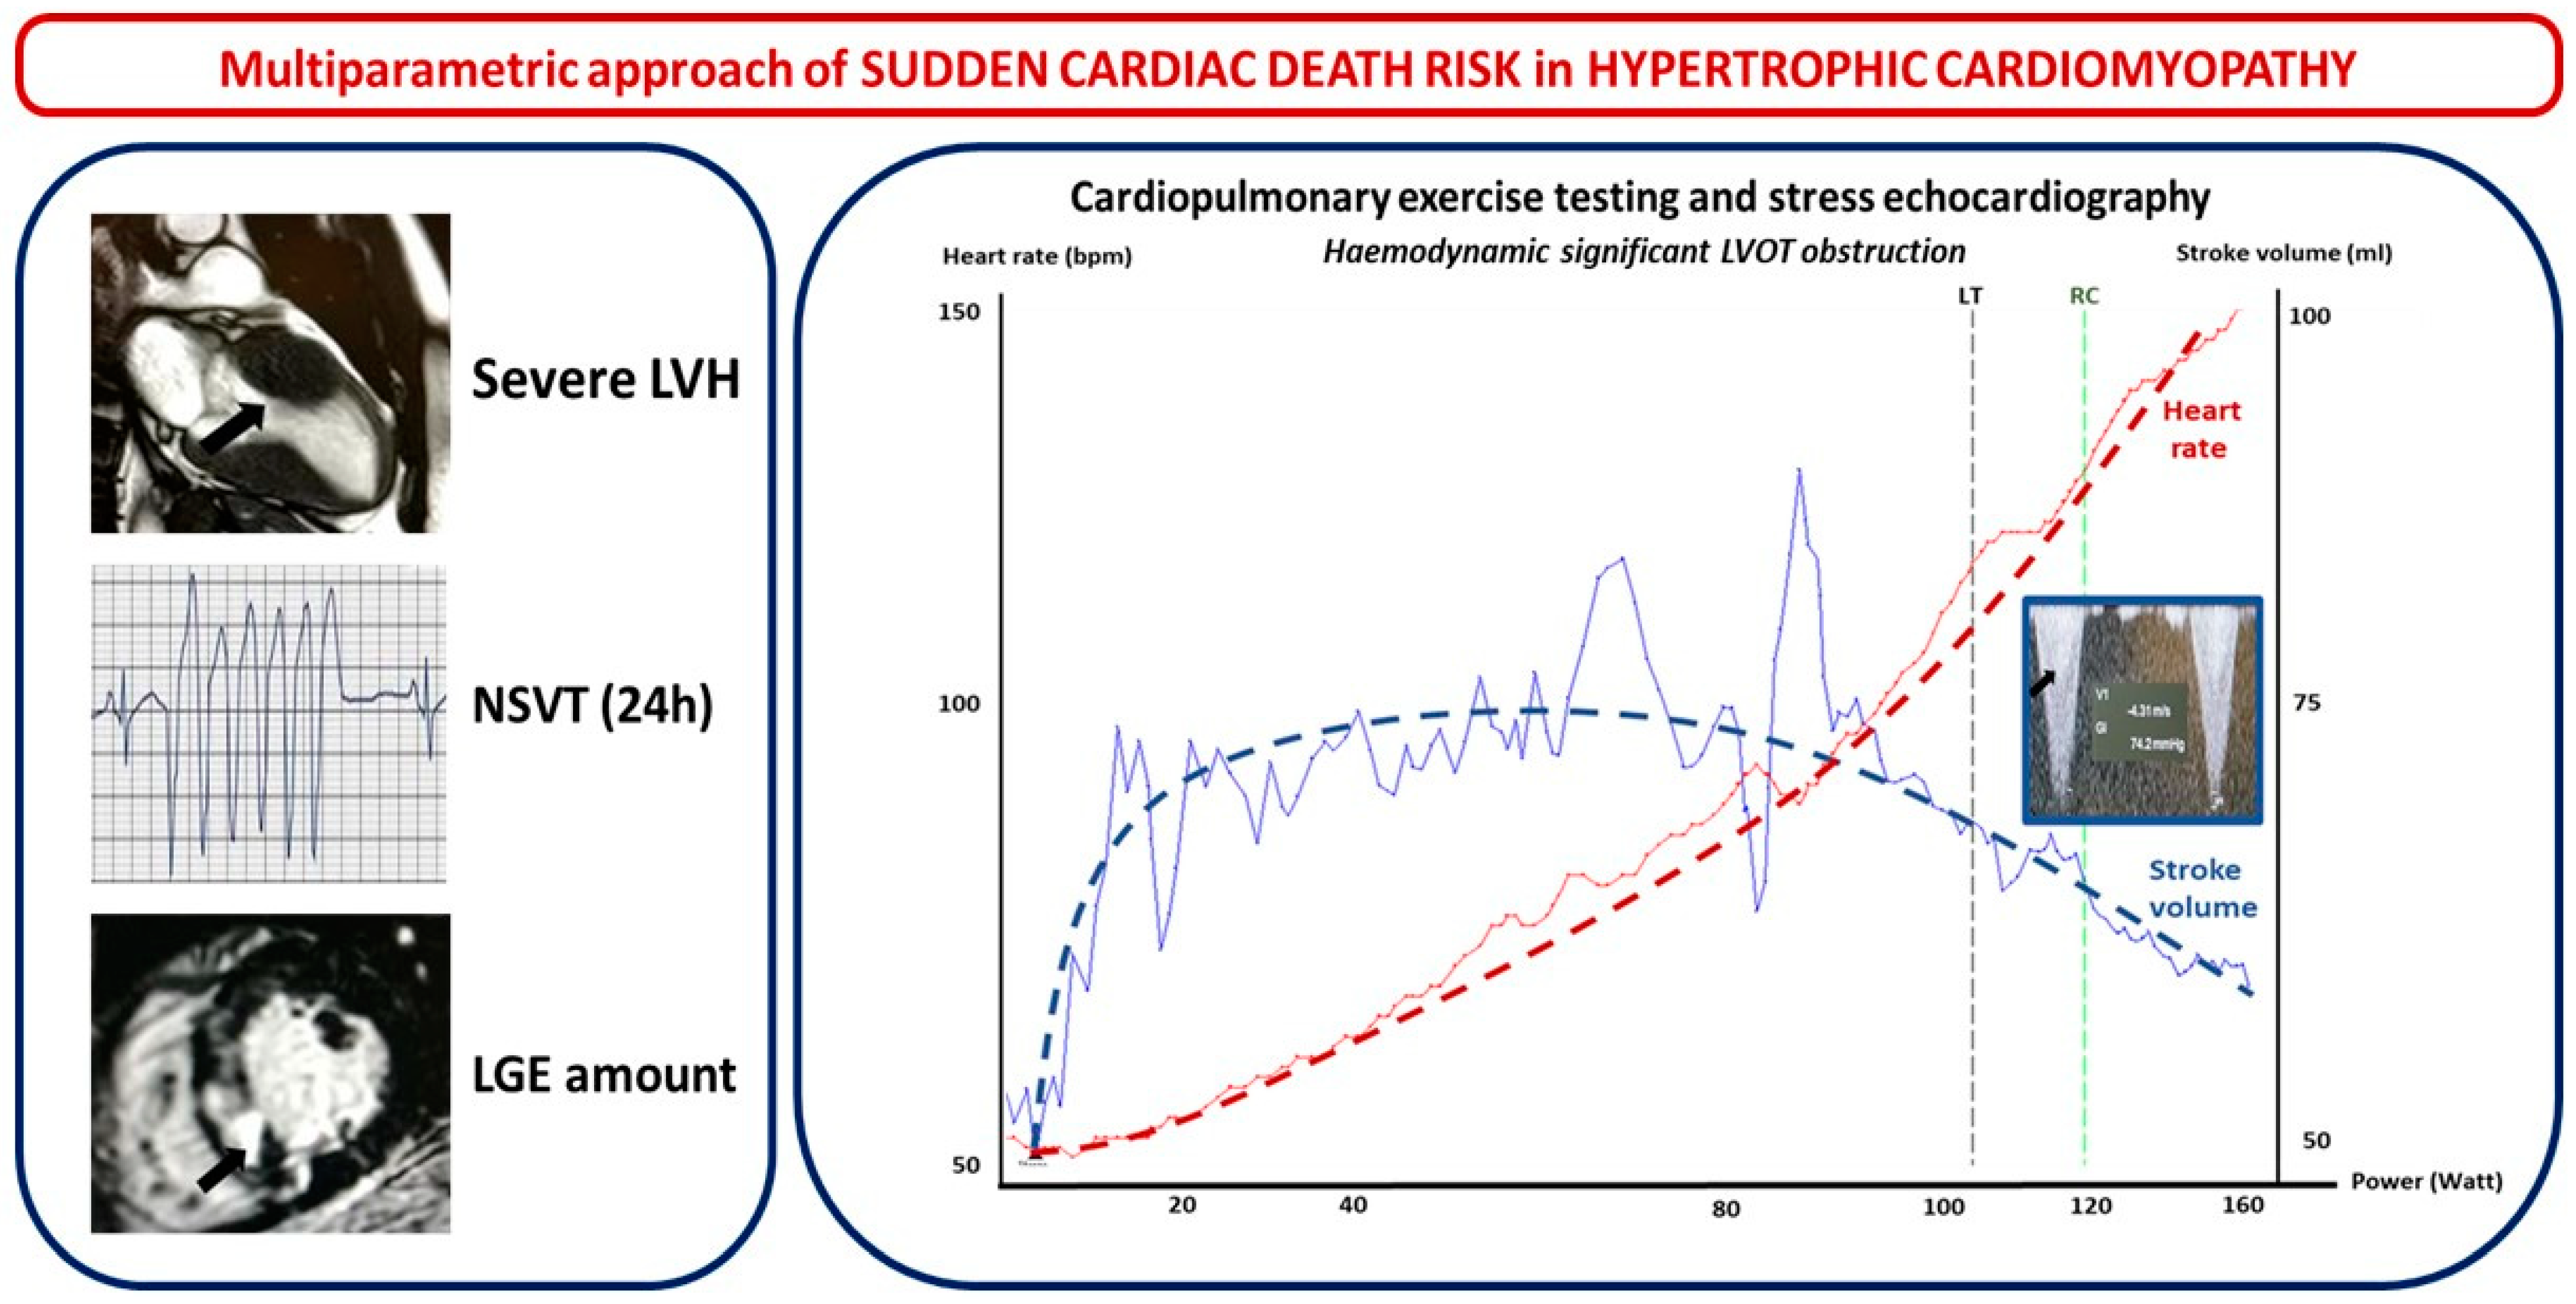

2.2.1. Hypertrophic Cardiomyopathy

- Left ventricle wall thickness (LVWT), involved segments, maximal wall thickness, and septal morphology. LVWT represents the hallmark of HMC and, while listed as a major risk factor for SCD in both the 2014 ESC and 2020 US guidelines, the latter only considered massive LV hypertrophy ≥ 30 mm in any LV segment as a major risk factor for SCD. In the HCM Risk-SCD model proposed by ESC 2014 guidelines, maximal LVWT was considered as a continuous rather than a dichotomous variable [12,13]. Different hypertrophy patterns have been observed. Based on the location of LV hypertrophy, Maron et al. initially proposed a four-type classification: Type I hypertrophy involves the basal septum; type II involves the whole septum; type III involves the anterior and anterolateral walls of the septum; and type IV involves LV apex. A five-phenotype classification has recently been suggested. It includes the following: type A, predominant mid-septal convexity toward the LV cavity (reverse septum HCM); type B, septum concavity toward the LV cavity and a prominent basal septal bulge (sigmoid septum HCM); type C, an overall straight septum (neutral septum HCM); type D, predominant apical distribution of hypertrophy (apical HCM); and type E, predominant hypertrophy at the mid-ventricular level (mid-ventricular HCM). Interventricular septum (IVS) morphology has been correlated with the probability of a positive genetic test for sarcomeric mutations: accordingly, a reverse IVS is associated with a high probability of a positive genetic test, apical or neutral IVS with a moderate probability, and a “sigmoid” IVS with a low probability of a positive test [18]. The addition of contrast echocardiographic agents could be useful in order to diagnose other localized forms of HCM (such as apical or inferolateral).

- LV apical aneurysm: US 2020 guidelines consider the presence of an LV apical aneurysm independent of its size as a major risk factor for SCD since it offers the substrate for re-entrant VT. Indeed, the prognosis of HCM patients with LV apical aneurysms is generally unfavorable, with an overall rate of life-threatening complications between 6% and 10% per year, mostly consisting of arrhythmic SCD and thromboembolic events [19,20].

- The mitral valve, its apparatus, and left ventricular outflow tract obstruction. More than 50% of HCM patients have abnormal mitral leaflets, and more than 25% show abnormalities of the chordae and papillary muscles as a primary phenotypic expression of HCM that may have a pivotal role in left ventricular outflow tract (LVOT) obstruction [21]. One of the parameters of the HCM Risk-SCD model is the maximal LV outflow tract (LVOT) gradient, while US guidelines, although not considering LVOT gradient in SCD risk, include the exercise-induced hypotension that represents its hemodynamic consequence. LVOTO at rest is present in about one-third of HCM patients and is an independent determinant of adverse prognosis [22]. In another one-third of HCM patients, LVOTO is only seen after provocative maneuvers, and treadmill echocardiography (EE) is a key method in detecting an inducible obstruction in HCM [13].

2.3. Step 3: ECG Monitoring and Exercise Testing in SCD Risk Evaluation

2.4. Step 4: Multimodality Imaging in SCD Risk Evaluation

2.4.1. Hypertrophic Cardiomyopathy